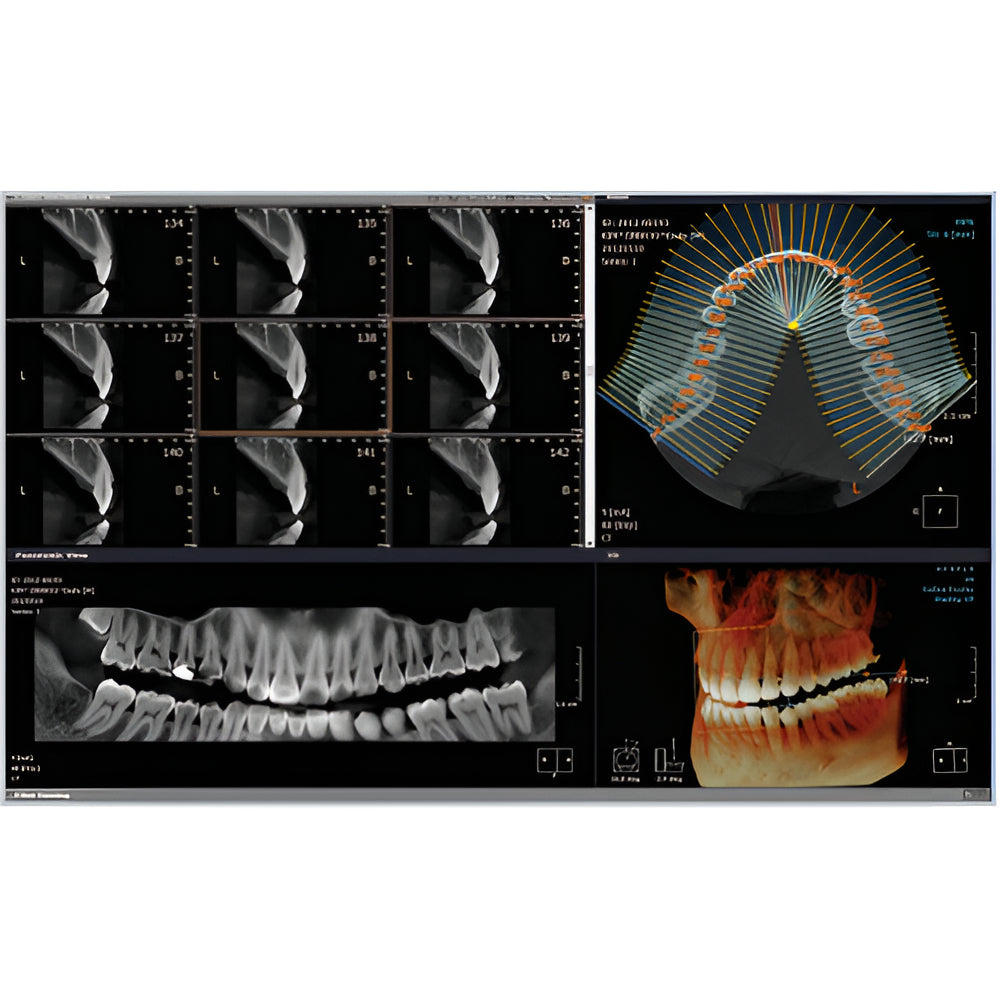

Rayscan Alpha brings another innovative technology with less Recon time and bigger FOV Size. And there are also new features – Fast scan mode, Object scan and Multi FOV.

- Field Of View: 9x9

- 2D/3D Imaging Software with License

- Panoramic

- Multiple Scan Modes